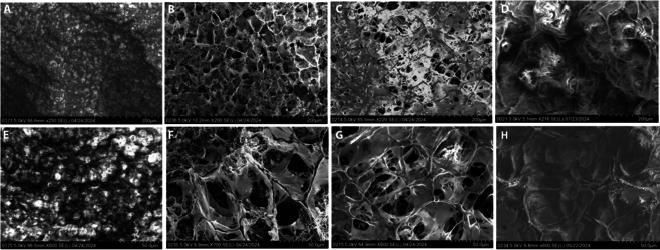

由HEPIA的Adrien

Roux领导的研究团队采用两种制造方法制备了四个10毫米的瓣叶原型。前三个瓣叶分别采用超高分子量聚乙烯(UHMWPE)、聚乙烯醇(PVA)涂层UHMWPE以及PVA和I型胶原蛋白涂层UHMWPE,通过传统的激光切割和冷冻干燥工艺制成。第四个瓣叶以及一个完整的二尖瓣植入物原型(命名为ValCard)则采用明胶甲基丙烯酸酯(GelMA)水凝胶,通过生物3D打印技术制成。研究团队在所有原型中都植入了从人类胎儿主动脉分离出的中胚层血管母细胞(AoMAB),这是一种干细胞亚群,与天然心脏组织中的瓣膜间质细胞具有相似的表型特征。

在传统制造工艺中,三层UHMWPE-PVA-胶原蛋白薄膜表现出最佳的整体性能。该薄膜在14天内的降解率为7.30±18.71%,且细胞增殖模式随时间推移最为稳定。研究发现,PVA和胶原蛋白涂层能够改变原本疏水的UHMWPE表面,引入表面粗糙度,从而在不影响材料机械性能的前提下,改善细胞黏附。GelMA基结构虽然表现出优异的细胞活力,并且与用于患者特定几何形状的体积3D生物打印具有良好的兼容性,但由于2毫米厚度的机械限制,被排除在降解和牵引力测试之外。